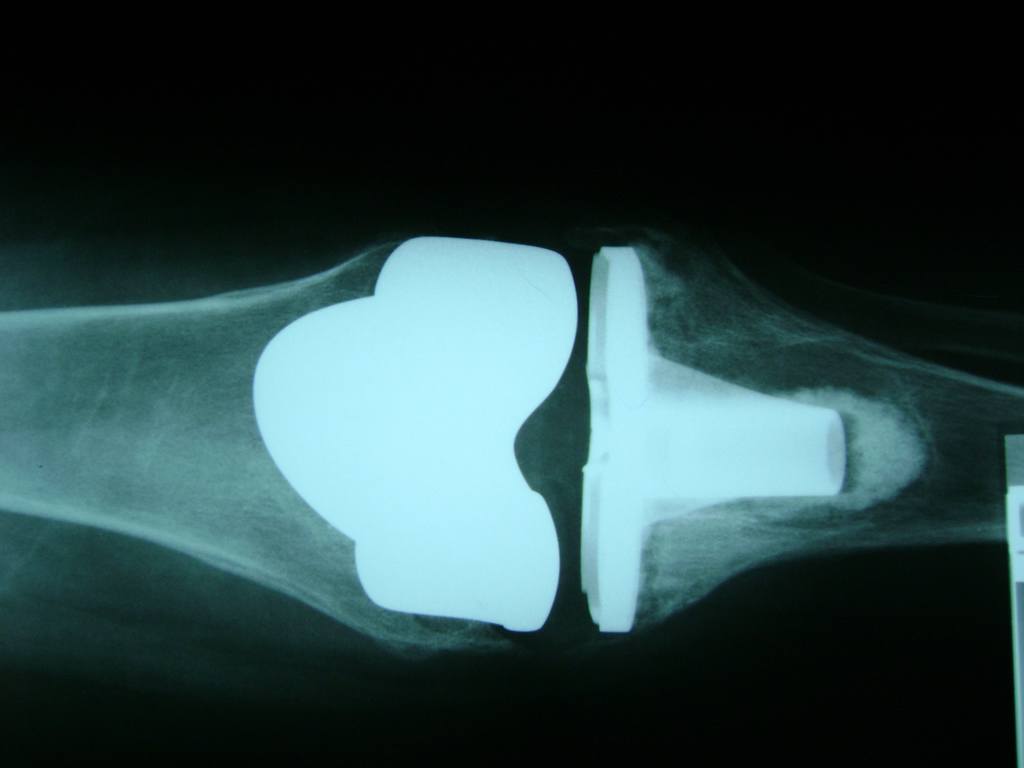

Cirugías de Codo - Rodilla

La artroscopia de rodilla es un cirugía en el cual la estructura interna de la articulación es examinada ya sea para realizar un diagnostico o para realizar un tratamiento, este procedimiento se realiza utilizando un instrumento parecido a un pequeño tubo llamado artroscopio.